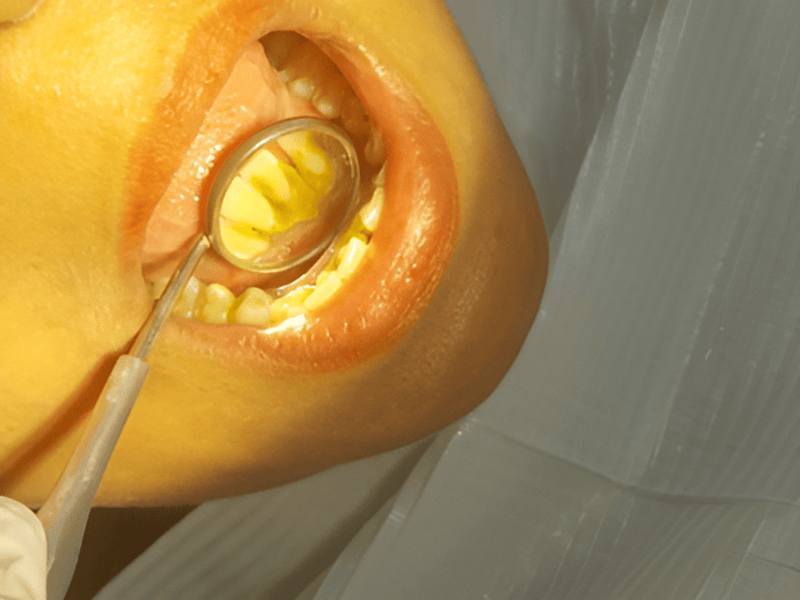

high standards of hygiene and comfort. Her expertise includes laser dentistry, cosmetic smile

makeovers, root canal treatments, teeth whitening, and full-mouth rehabilitation. She believes in

From routine checkups to complex gum treatments, dental implants, laser dentistry, root canal treatments (RCT), and smile

Dr. Bhardwaj specializes in Periodontics, offering treatments for gum diseases, dental implants, laser dentistry, root canal treatments (RCT), teeth whitening, smile makeovers, and general dental care.